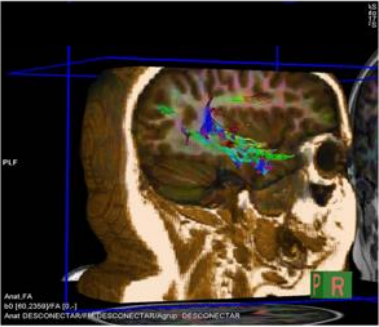

2. Superior insular sulcus: separates the insula from the fronto-parietal cortex, and its main relationships are: the ventricular system, the basal ganglia and the corona radiata with its projection fibers10. As mentioned previously, this sulcus is used as a reference to perform hemispheric deafferentation in hemispherotomies for the treatment of epilepsy. In these procedures, the surgeon moves towards the ventricular system following the superior sulcus, thereby severing the fibers of the corona radiata11. Thus, the relationship of this sulcus can be seen with conventional MRI images1 and with tractography11 (Figure 11 and 12).

Figure 11: anatomical preparation, sagittal section.

Figure 12: MRI tractography, descending fibers.